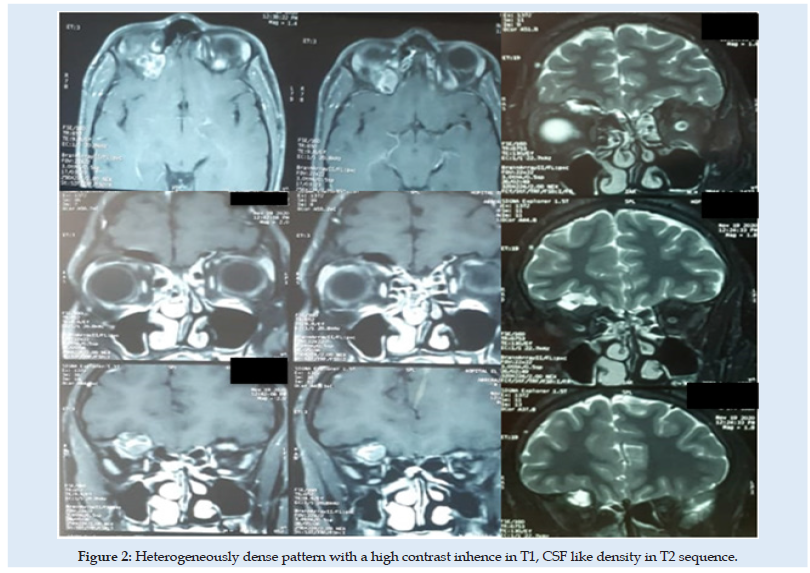

A 17-year-old man was referred to our hospital for a nonpulsatile, painless right eye exophtalmy. His acuity and field of vision were both normal. A CT scan revealed an expansile bone mass and cystic swelling on the right orbital roof Figure 1. An orbital MRI revealed a homogeneously dense pattern with a high contrast inhence in T1 Figure 2. The right globe and optic nerve were not damaged, the all was suggestive of an aneurysmal bone cyst. We decided to remove the lesion because of the right proptosis using a right extradural subfrontal approach Figure 3. No reconstitution of the orbital roof was required. The regression of the exophtalmy highlighted, the post-operative findings. The histopathological concluded to a FD. A six months follow-up, didn’t show any abnormal sensations or pain. There was no proof of tumoral recurrence.

Figure 2: Heterogeneously dense pattern with a high contrast inhence in T1, CSF like density in T2 sequence.